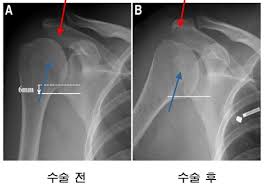

영상 검사

신체 검사 결과에 따라 추가적인 영상 검사가 필요할 수 있습니다. 일반적으로 사용되는 검사 방법에는 ▶️ X-레이, ▶️ 초음파, ▶️ MRI 등이 있습니다. X-레이는 뼈의 상태를 확인하는 데 도움을 주고, 초음파는 연조직의 구조와 상태를 파악하는 데 유용합니다. MRI는 보다 상세하게 손상의 정도를 평가할 수 있어 회전근개 파열 진단에서 특히 유용합니다.

수술적 치료

비수술적 치료에도 불구하고 증상이 계속될 경우, 수술적인 치료가 필요할 수 있습니다. 수술의 목적은 손상된 회전근개를 복구하고 어깨의 정상 기능을 회복하는 것입니다. 일반적으로, 이 과정은 내시경(subacromial decompression)을 통한 최소 침습 방법으로 진행됩니다. 수술 후에도 꾸준한 물리 치료와 재활 운동이 필수적입니다.